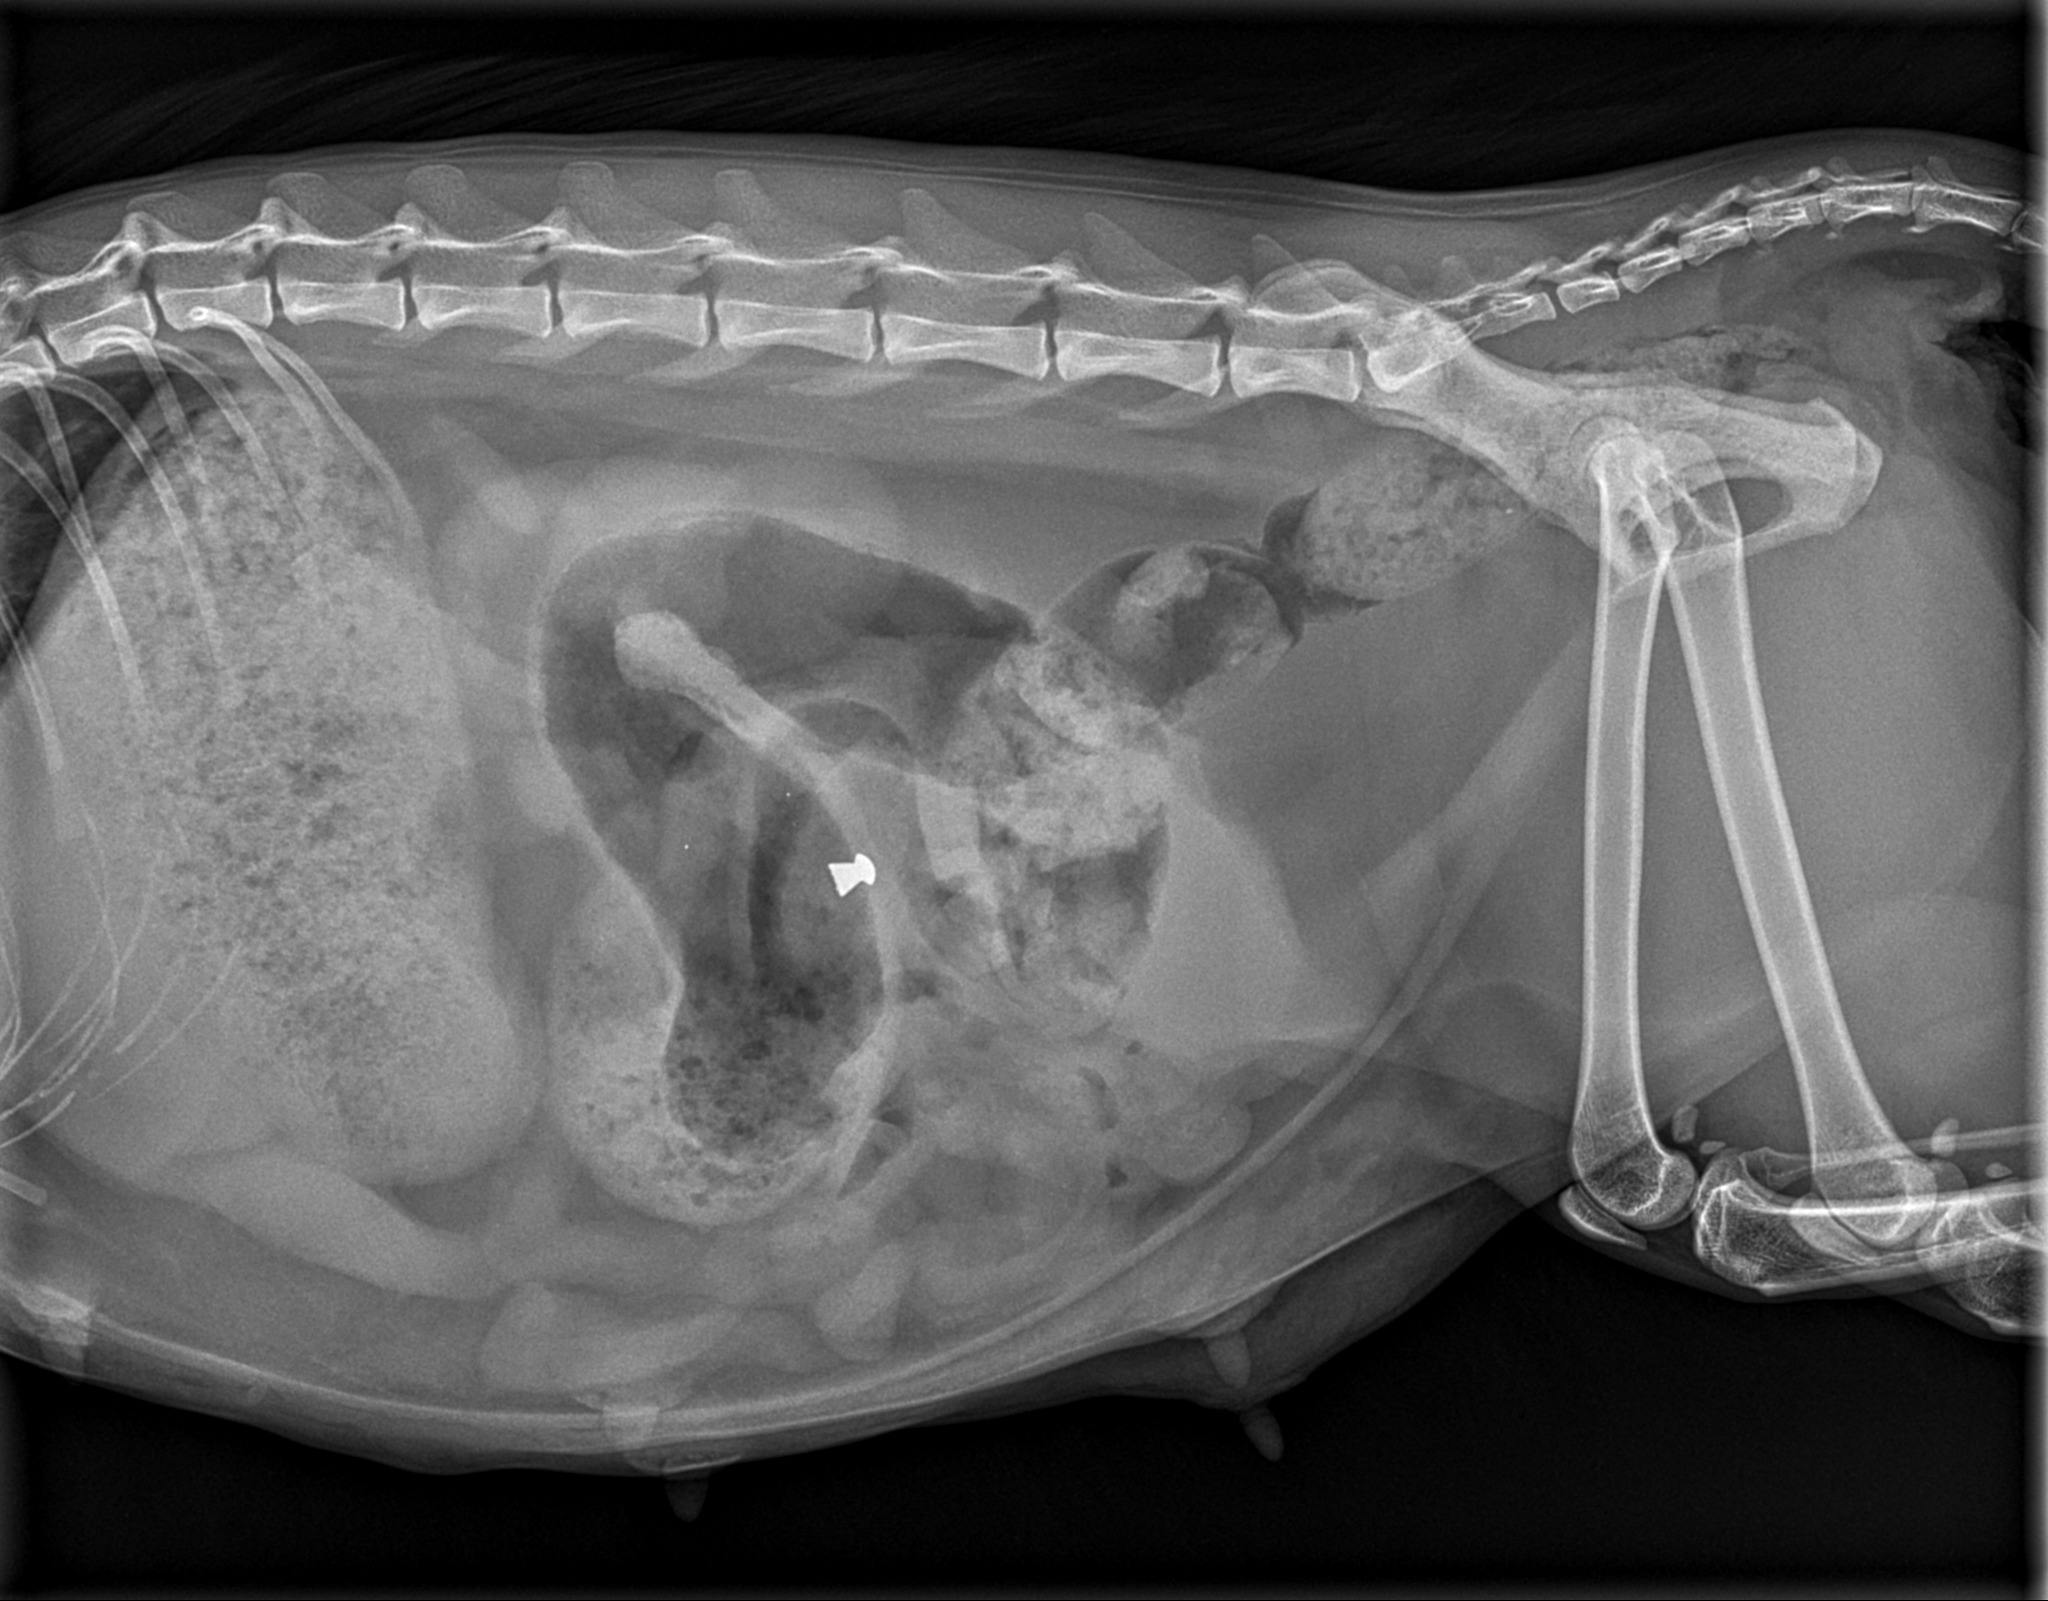

- Hun bliver derfor sendt i røntgen og her opdager vi med gru, at hun er blevet skudt med et luftgevær, skriver Nordjyllands Internat og Pension på Facebook.

Efter Mutti havde født sine to killinger opdagede internatet en kugle på under huden på katten.